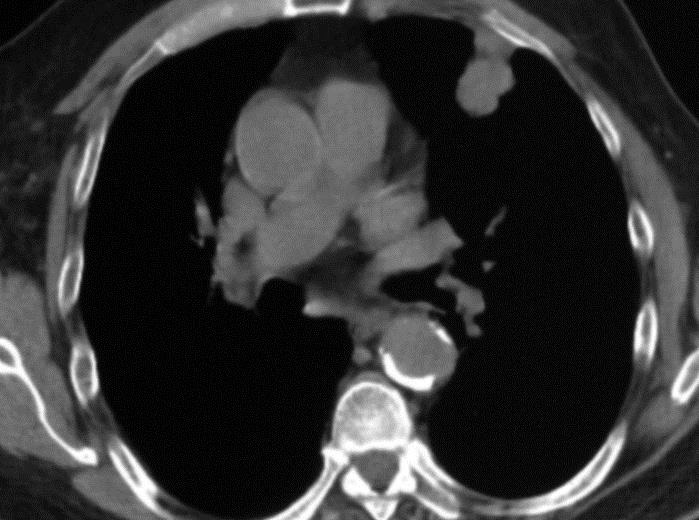

病例2